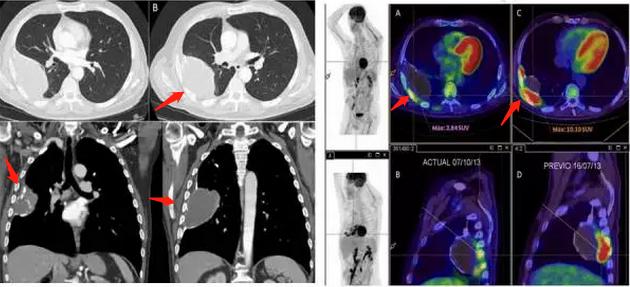

他并未采取治疗,在3个月后复查,发现病灶周围长出不规则软组织密度影,做了PET-CT发现高摄取:

图中黄色发亮的地方,都是新生组织,后来经CT引导下穿刺活检,病理证实为脓胸相关恶性淋巴瘤。

上图是一位54岁的男子,结核性脓胸40年,活检确诊为脓胸相关恶性淋巴瘤。